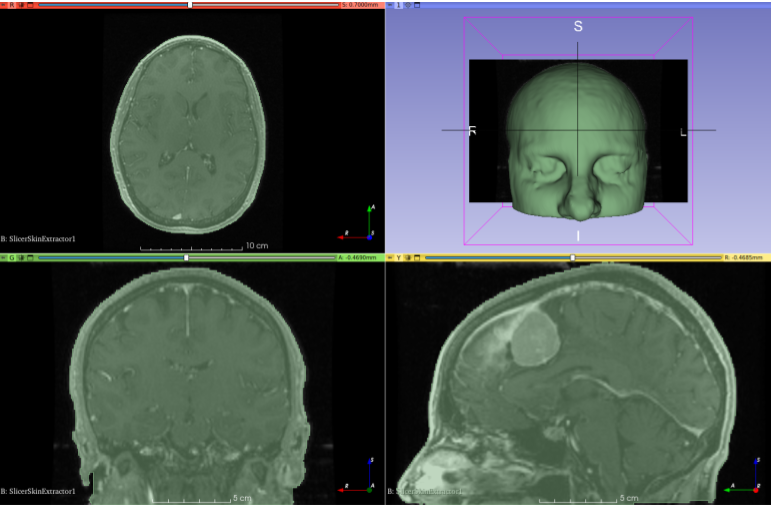

Example of skin surface extraction using Slicer